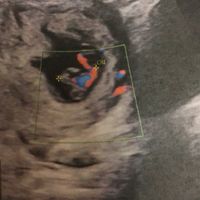

Sono qui a raccontavi la mia storia .. Sono una ragazza di 25 sposata da tre mesi Con un aborto ritenuto a 9 settimane a maggio del 2019.La voglia era tanta è così a settembre per fortuna mi sono...